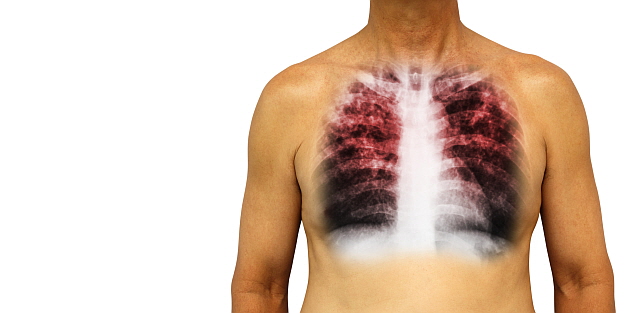

안녕하세요! 오늘은 ‘폐렴’의 증상에 대해 자세히 알려드릴게요

요즘처럼 일교차가 크고 면역력이 떨어지기 쉬운 계절에는

감기나 독감 뒤에 폐렴으로 악화되는 경우도 많습니다.

폐렴 증상 폐렴 증상

폐렴 증상 3. 호흡 곤란 및 숨 가쁨

폐에 염증이 생기면 산소 교환이 어려워져

숨이 차고 가슴이 조이는 느낌,

또는 평소보다 가쁜 숨, 짧은 호흡이 나타날 수 있어요.

폐렴 증상 9. 입술이나 손끝이 푸르스름하게 변색 (청색증)

산소 포화도가 낮아지면서

입술, 손톱, 발끝이 보랏빛 또는 푸르스름하게 변하는 청색증이 생길 수 있습니다.

이는 폐렴이 상당히 진행된 상태일 수 있으므로 응급 상황입니다.10. 구토, 설사 등 소화기 증상